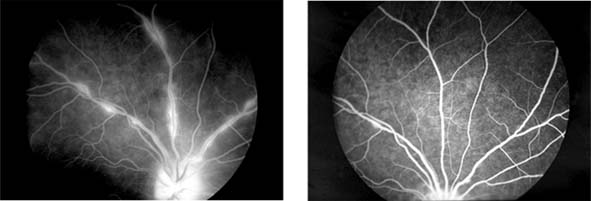

The appearance of the fundus in hypertensive retinopathy is determined by the degree of elevation of the blood pressure and the state of the retinal arterioles. Thus, in young patients with accelerated hypertension, an extensive retinopathy is seen, with hemorrhages, retinal infarcts (cotton-wool spots), choroidal infarcts (Elschnig's spots), and occasionally serous detachment of the retina (Figure 15-10). Severe disk edema is a prominent feature. Vision may be impaired but is restored if blood pressure is reduced with caution.

Figure 15-10

Figure 15-10: Accelerated hypertension. Fluorescein angiogram in a young man showing arteriolar constriction, dilation of capillaries with microaneurysms, and areas of closure. Marked disk edema is present.

In contrast, elderly patients with arteriosclerotic vessels are unable to respond in this manner, and their vessels are thus protected by the arteriosclerosis. It is for this reason that elderly patients seldom exhibit florid hypertensive retinopathy (Figure 15-11).

Figure 15-11

Figure 15-11: Accelerated hypertension. Fluorescein angiogram in an elderly wom.an showing marked arteriolar constriction and irregularity but few signs of florid retinopathy.

Fluorescein angiography has made possible accurate documentation of these microcirculatory changes. In young patients with hypertension, arteriolar attenuation and occlusion are seen, and capillary nonperfusion can be verified in relation to a cotton-wool spot, which is surrounded by abnormal dilated capillaries and microaneurysms with increased permeability on fluorescein angiography.

Resolution of the cotton-wool spots and the arteriolar changes occurs with successful hypotensive therapy. In elderly patients, the underlying arteriosclerotic changes are irreversible.